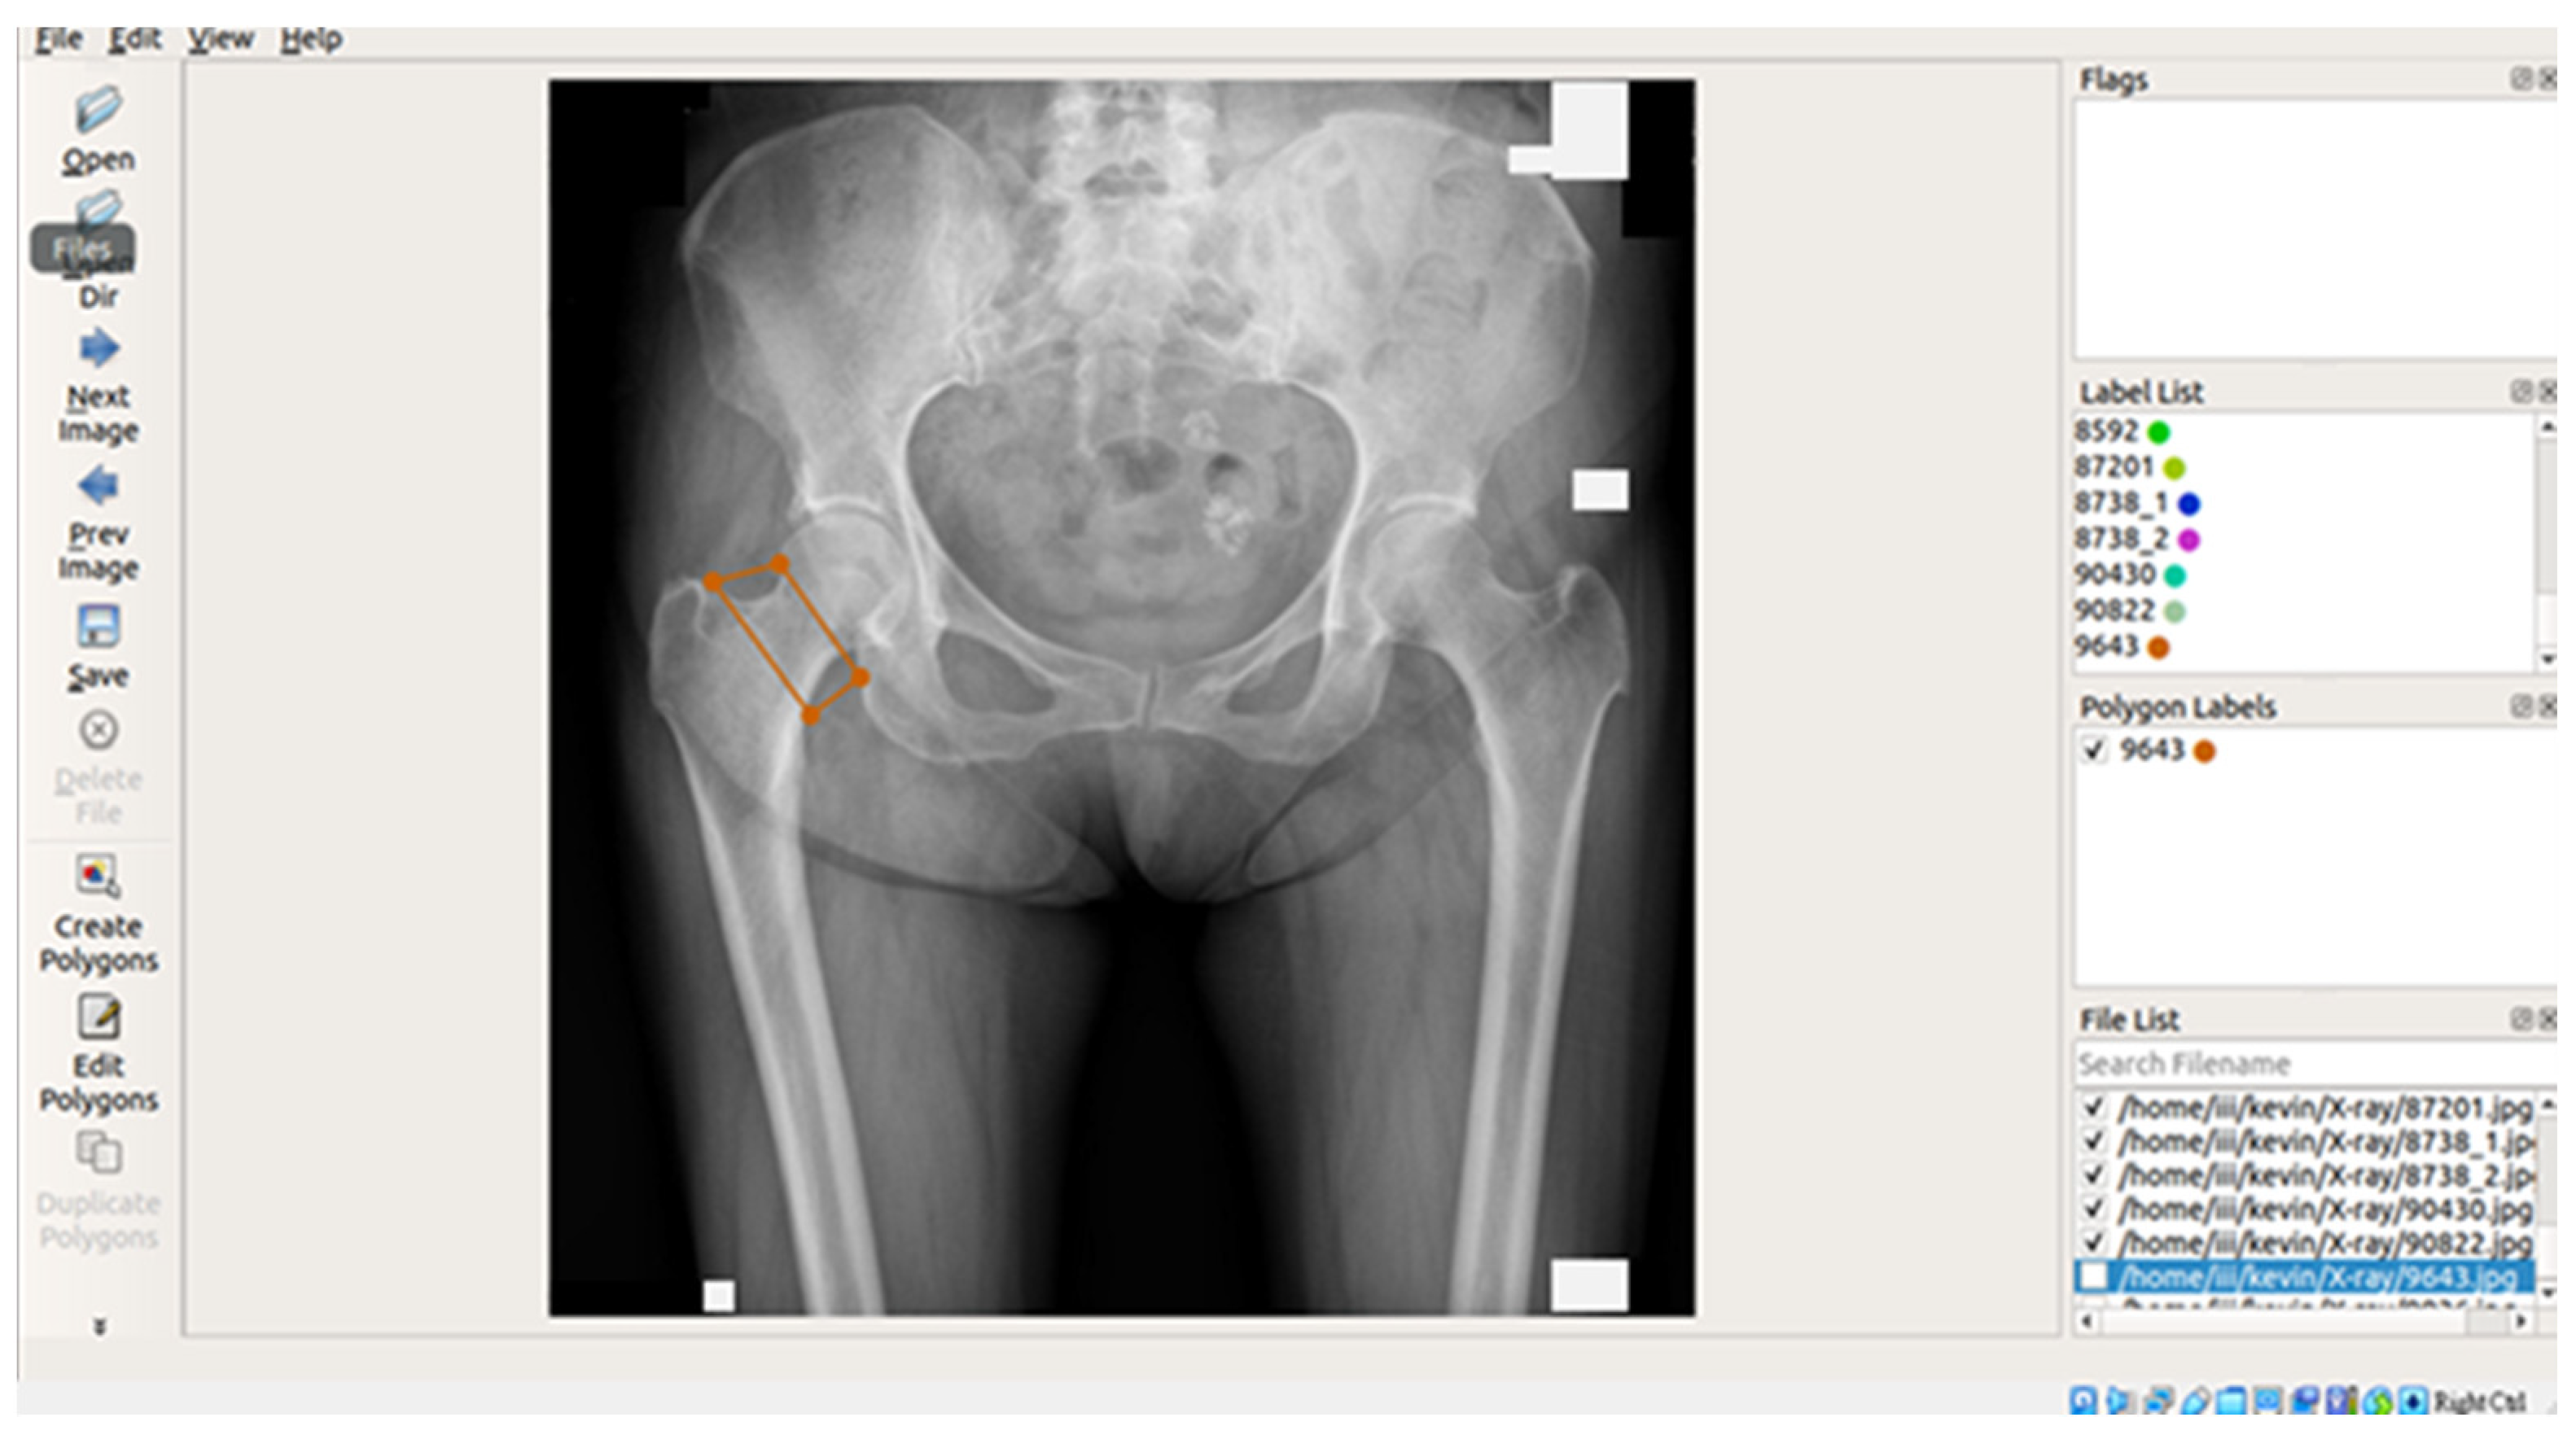

In this study, X-ray images of each of the four areas of the patient’s hip (femoral neck, greater trochanter, Ward’s triangle, and total hip) were separated and manually labeled using Labelme, an open-source tool that can be used for labeling [29]. The four parts of the hip were then framed as shown in Figure 2 below, and the labeled image data were batch converted into binary png files, which were used as inputs for the supervised learning training of U-Net, U-Net++, and image categorization in the image segmentation process.

Figure 2.

Image labeling tool and interface.